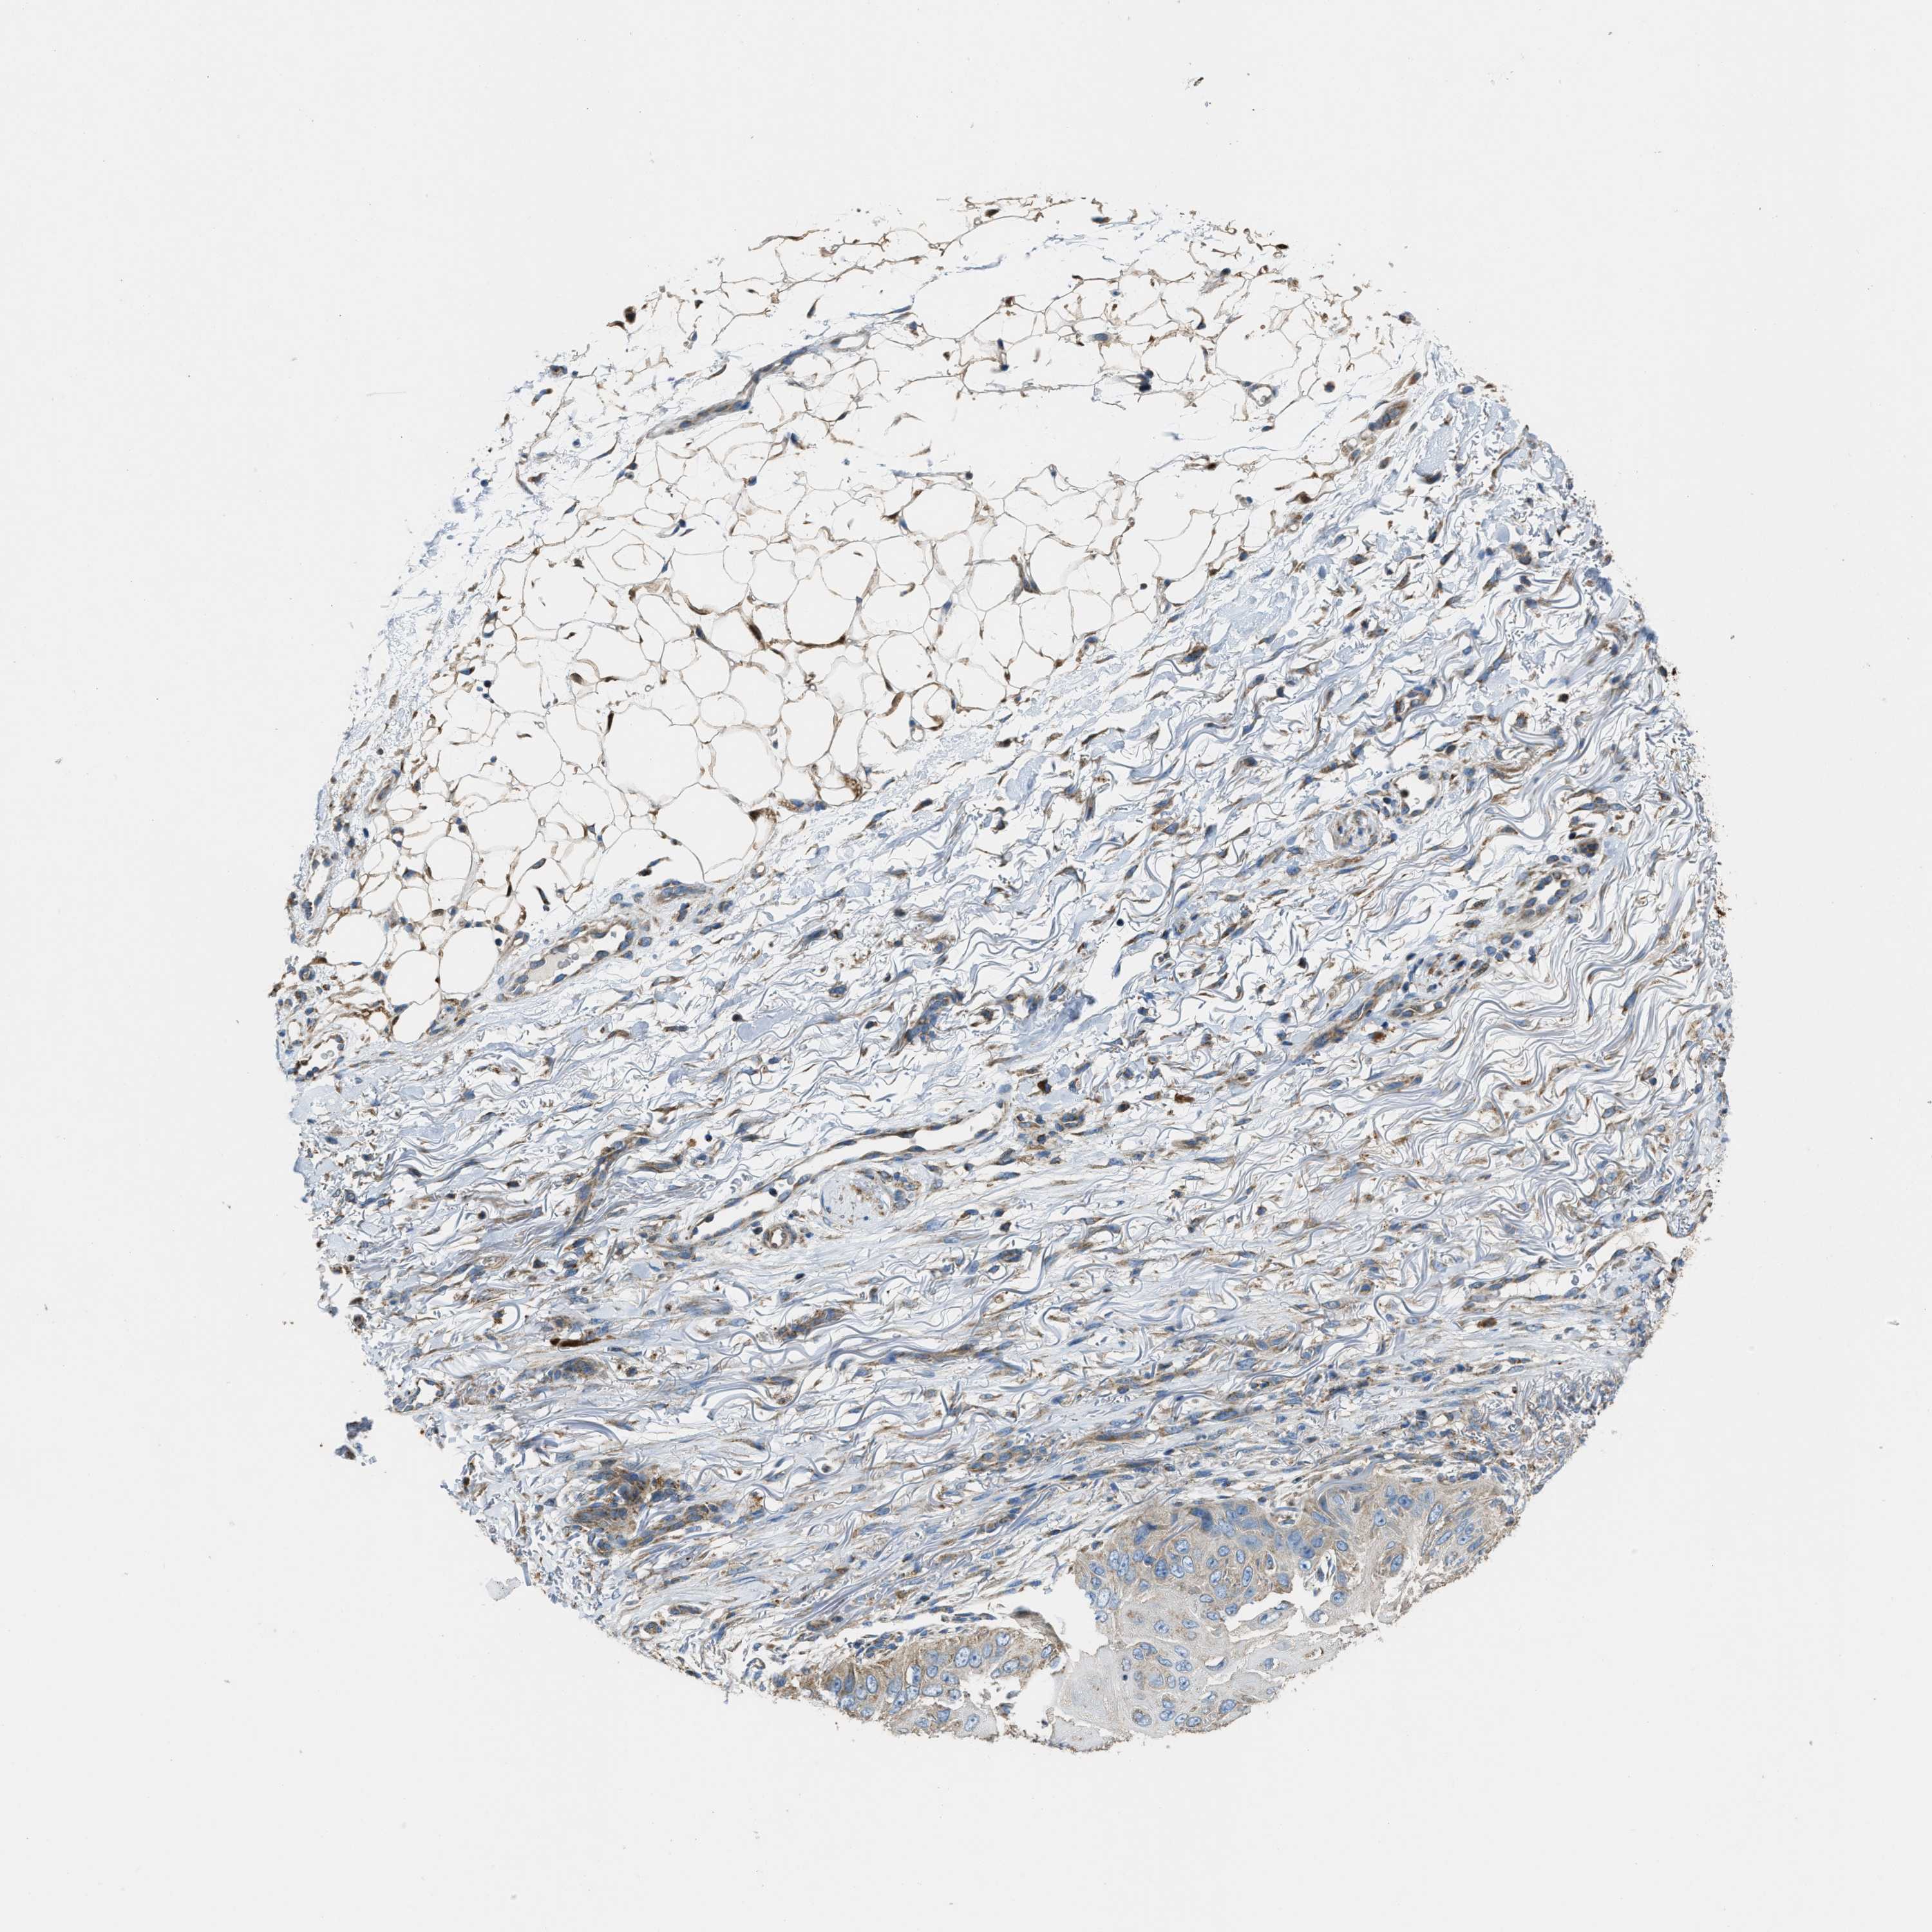

Basal cell and squamous cell cancer

SKIN CANCER - Protein expressioni

A mouse-over function shows sample information and annotation data. Click on an image to view it in a full screen mode. Samples can be filtered based on level of antibody staining by selecting one or several of the following categories: high, medium, low and not detected. The assay and annotation is described here.

Antibody stainingi

Antibody staining in the annotated cell types in the current human tissue is reported as not detected, low, medium, or high, based on conventional immunohistochemistry profiling in selected tissues. This score is based on the combination of the staining intensity and fraction of stained cells.

Each image is clickable and will lead to virtual microscopy that enables deeper exploration of all samples and also displays staining intensity scores, fraction scores and subcellular localization as well as patient and tissue information for each sample.

Antibody HPA021167

Staining

High

Medium

Low

Not detected

Intensity

Strong

Moderate

Weak

Negative

Quantity

>75%

75%-25%

<25%

None

Location

Nuclear

Cytoplasmic/membranous

Cytoplasmic/membranous,nuclear

Squamous cell carcinoma, metastatic, NOS